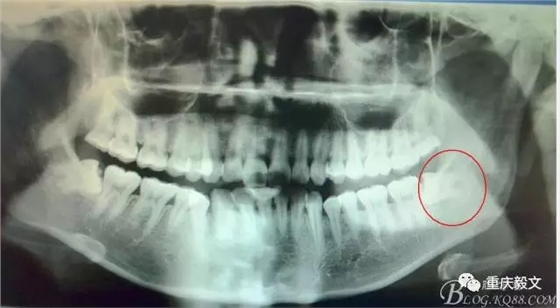

圖1.全景片檢查:38水平位、雙根、分叉大。